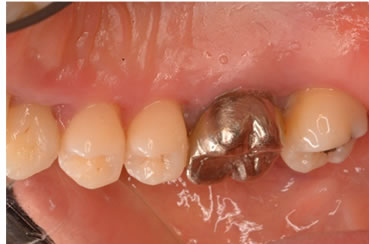

症例4

治療の特徴(患者I様)

初診時においては物を咬むと違和感が強く歯周外科処置を行いました。

骨のラインが部分的に増え、平坦にきれいに治っています。

2019年5月20日現在